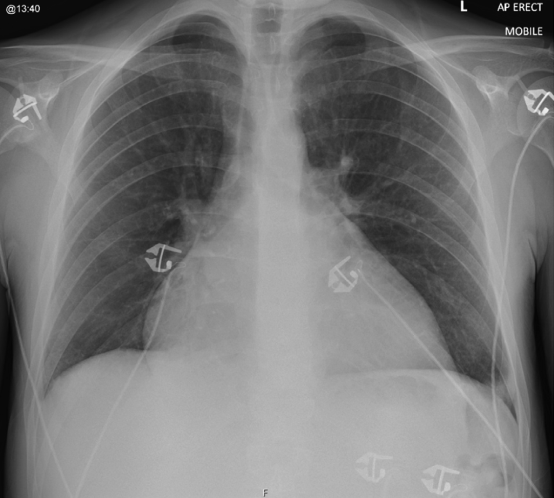

圖:入院胸部X光可見心影擴大/BMJ case report